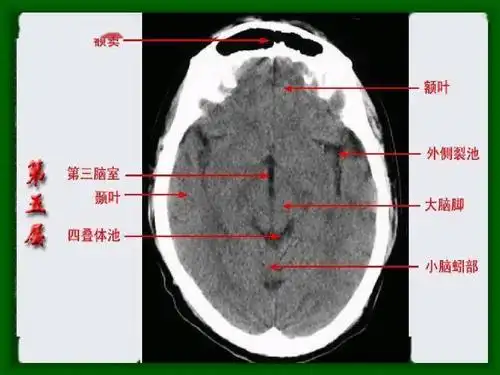

头颅ct解剖与常见出血梗死判读